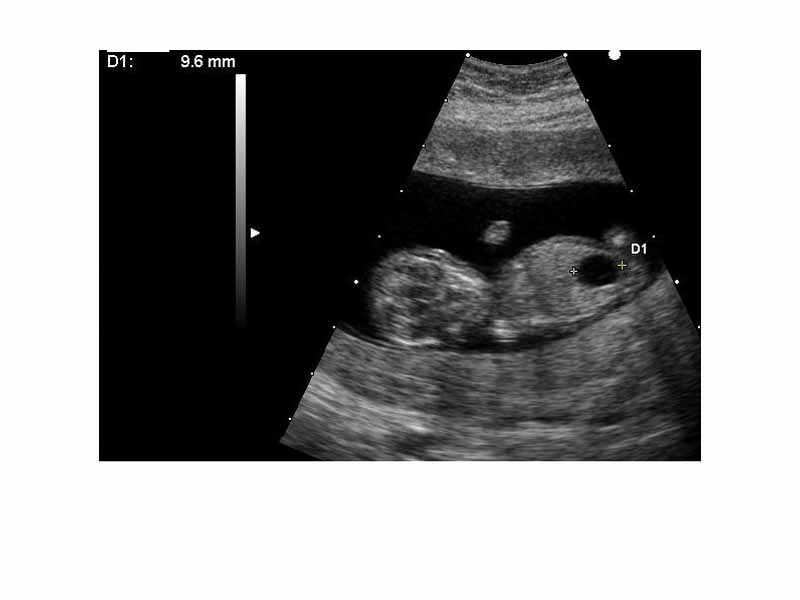

Ultrasound of fetus with Down syndrome and megacystis